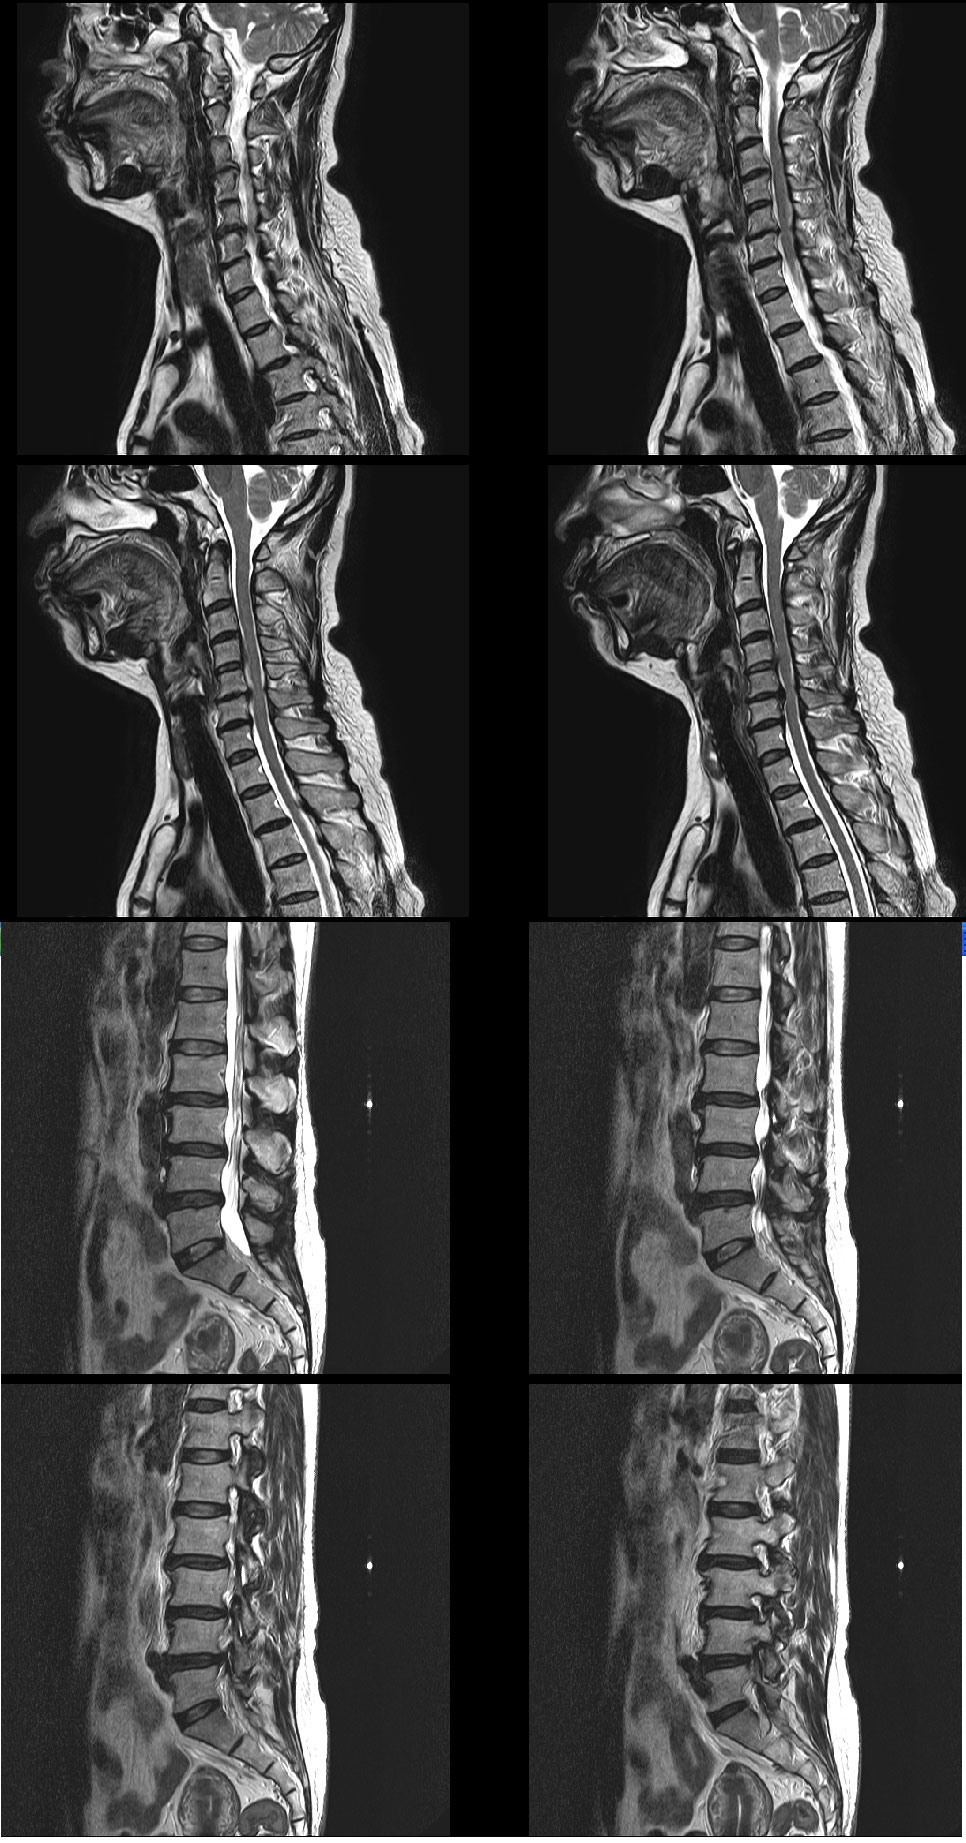

ڼ ũ 㸮ũ mri Ϸ پ 2 ϱ |